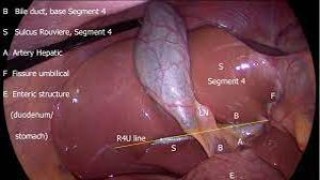

Anatomy of Triangle Doom